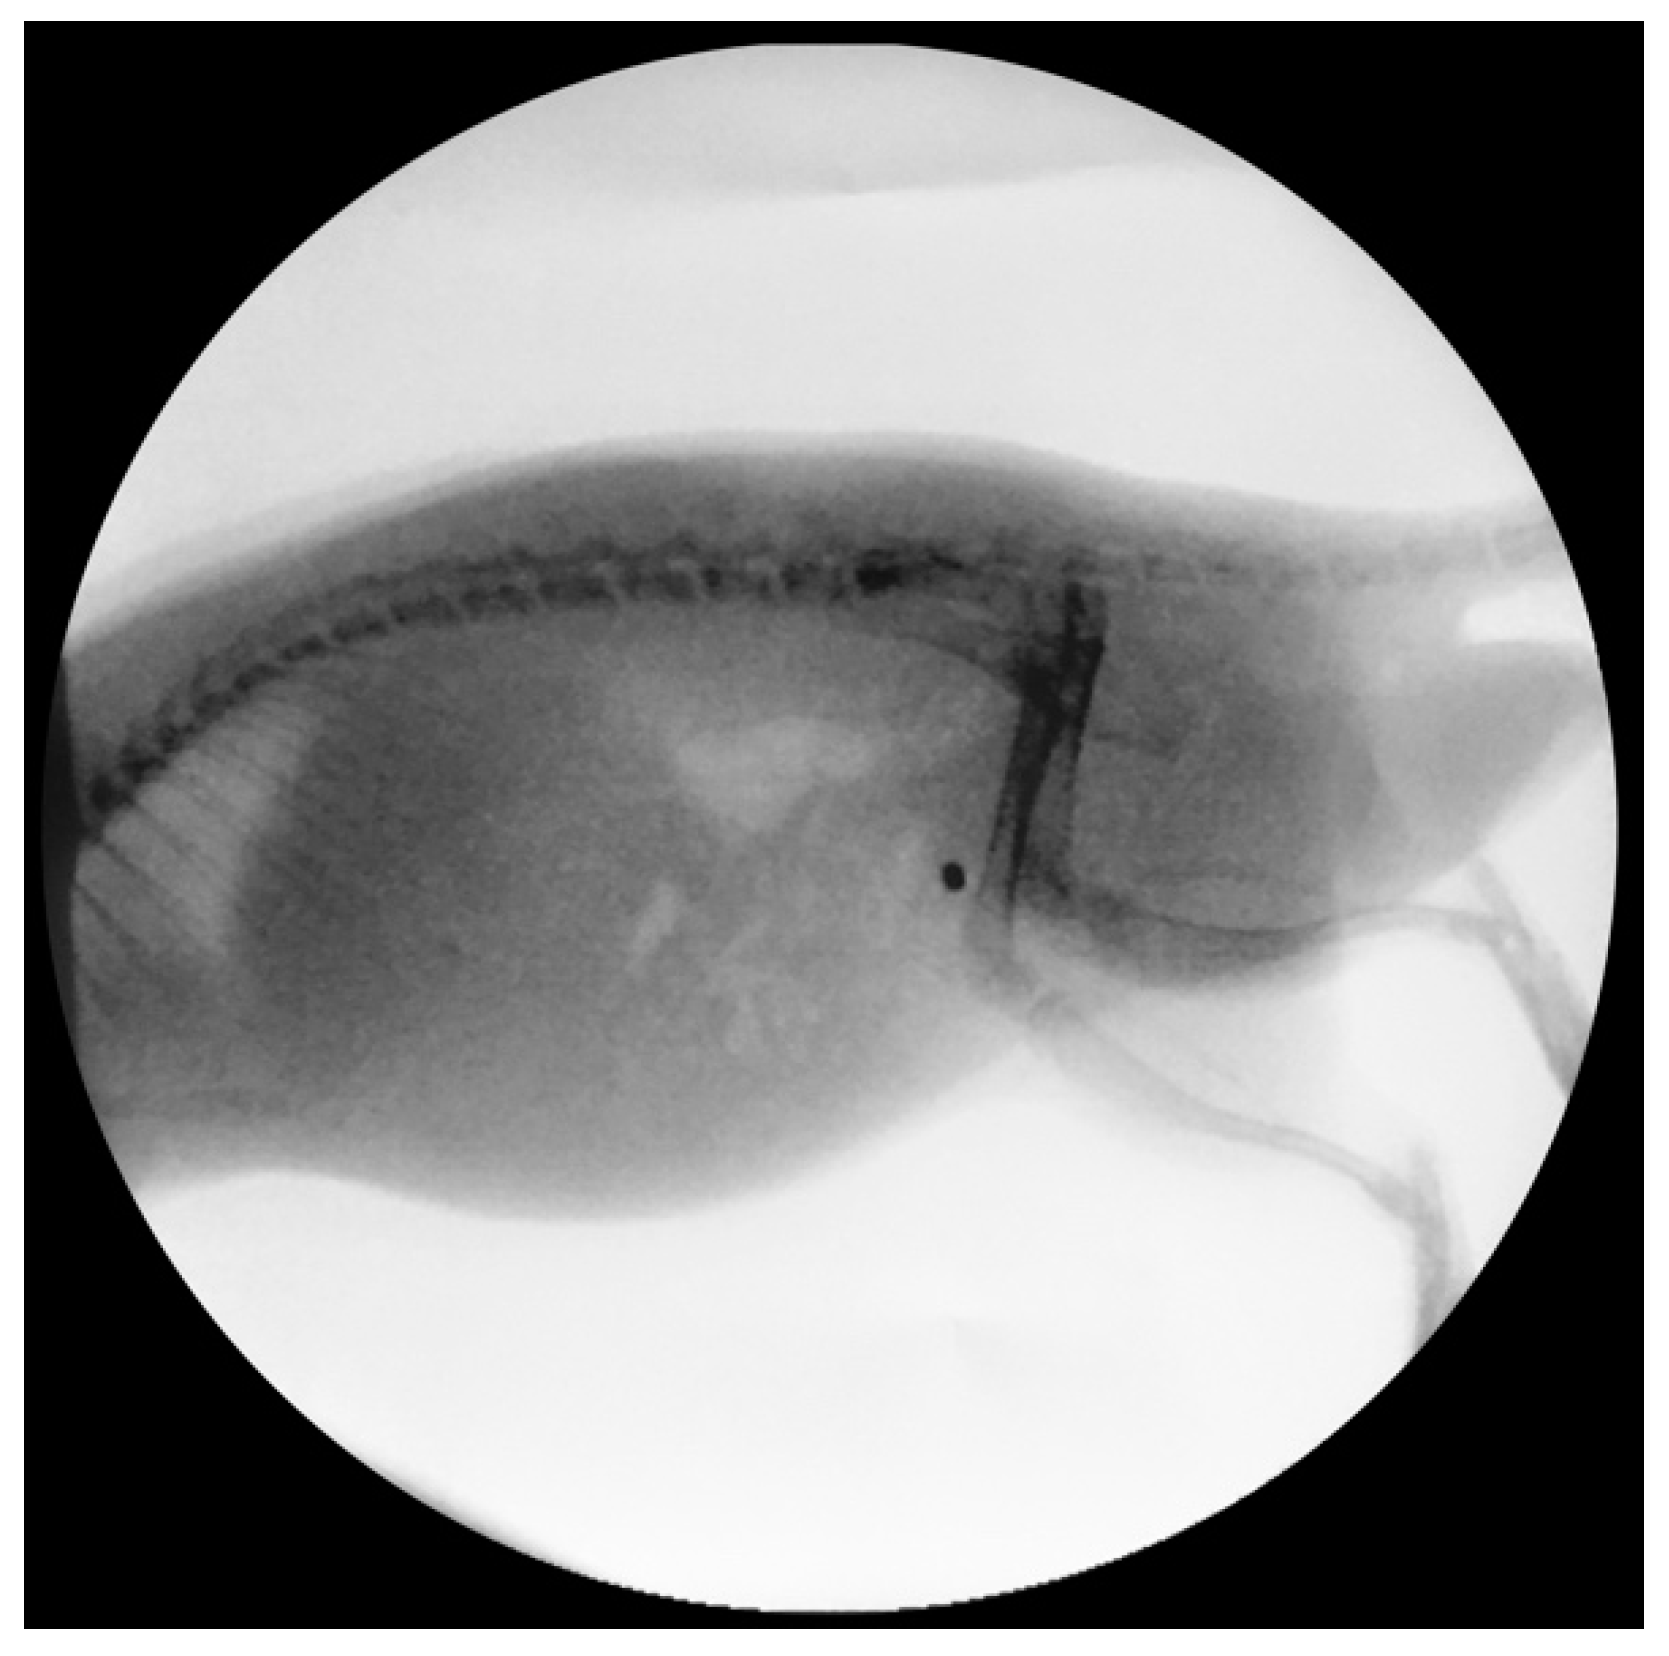

3.2.2. Encrustation of Elastollan with a-C:H/Cu-Mulitilayer Coating

- Kartal, I.G.; Baylan, B.; Gok, A.; Sagnak, A.L.; Karakoyunlu, N.; Cakici, M.C.; Kaymak, S.; Karabacak, O.R.; Topaloglu, H.; Ersoy, H. The Association of Encrustation and Ureteral Stent Indwelling Time in Urolithiasis and KUB Grading System. Urol. J. 2018, 15, 323–328. [Google Scholar] [CrossRef]

- Kawahara, T.; Ito, H.; Terao, H.; Yoshida, M.; Matsuzaki, J. Ureteral stent encrustation, incrustation, and coloring: Morbidity related to indwelling times. J. Endourol. 2012, 26, 178–182. [Google Scholar] [CrossRef] [PubMed]

- Arenas, J.L.; Shen, J.K.; Keheila, M.; Abourbih, S.R.; Lee, A.; Stokes, P.K.; Li, R.; Alsyouf, M.; Lightfoot, M.A.; Baldwin, D.D. Kidney, Ureter, and Bladder (KUB): A Novel Grading System for Encrusted Ureteral Stents. Urology 2016, 97, 51–55. [Google Scholar] [CrossRef]